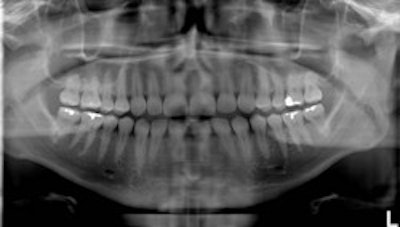

Top, standard panoramic image from a PC-1000 system using a CdTe sensor from Ajat and the PanoACT-1000 tomosynthesis software. Middle, although the anterior teeth are distorted, the posterior teeth no longer have overlapped interproximals. By manually positioning the patient in the system, the contacts are now open. Bottom, the tomosynthesis software then autocorrected the image to bring the front teeth into focus. All images courtesy of Dr. Robert Langlais. |

"In ordinary digital imaging, the software can make the image lighter or darker, change the contrast, magnify, zoom, copy, etc.," he said. "This software goes beyond that. It will autocorrect for positioning errors and generate a new image that is better than the original image. This is a software function that other digital imaging software just can't do."